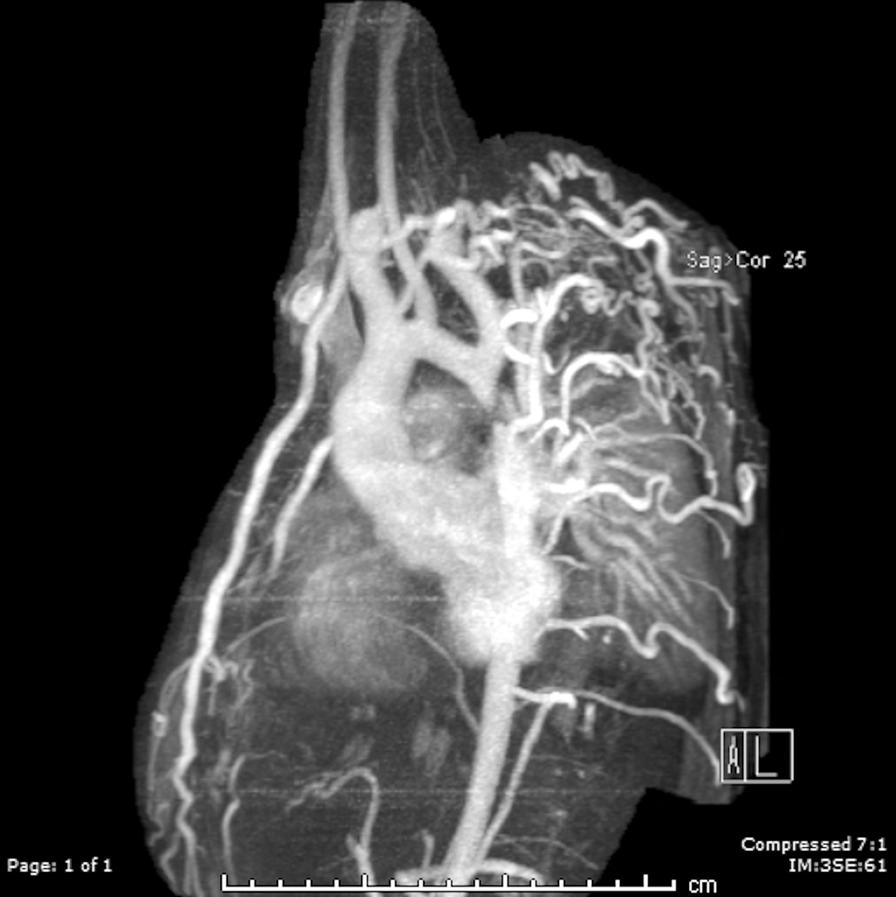

Cardiovascular magnetic resonance (CMR) has been utilized in the management and care of pediatric patients for nearly 40 years. It has evolved to become an invaluable tool in the assessment of the littlest of hearts for diagnosis, pre-interventional management and follow-up care. Although mentioned in a number of consensus and guidelines documents, an up-to-date, large, stand-alone guidance work for the use of CMR in pediatric congenital 36 and acquired 35 heart disease endorsed by numerous Societies involved in the care of these children is lacking. This guidelines document outlines the use of CMR in this patient population for a significant number of heart lesions in this age group and although admittedly, is not an exhaustive treatment, it does deal with an expansive list of many common clinical issues encountered in daily practice.

心血管磁共振(CMR)在儿科患者的管理和护理中已经应用了近 40 年。它已经发展成为评估最小的心脏的宝贵工具,用于诊断、介入前管理和随访。尽管在许多共识和指南文件中提到,但在儿科先天性心脏病和后天性心脏病领域,目前还缺乏一份由众多参与儿童护理的学会共同认可的、最新的、独立的、针对 CMR 使用的大型指南。本指南文件概述了 CMR 在该年龄段的许多心脏病变中的应用,尽管不能说是详尽的治疗方法,但它确实涉及了在日常实践中经常遇到的许多常见临床问题的广泛列表。